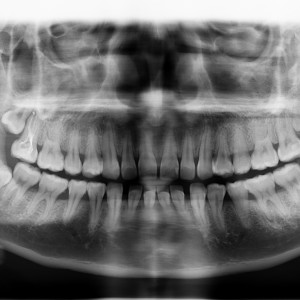

廈門拜博口腔醫(yī)院醫(yī)生張忠做牙齒隱形矯正怎么樣?附案例效果對比圖

術(shù)前

更新時(shí)間:2021-07-29 16:54:58 項(xiàng)目:#牙齒矯正 所屬醫(yī)院:廈門拜博口腔醫(yī)院 所屬醫(yī)生:張忠